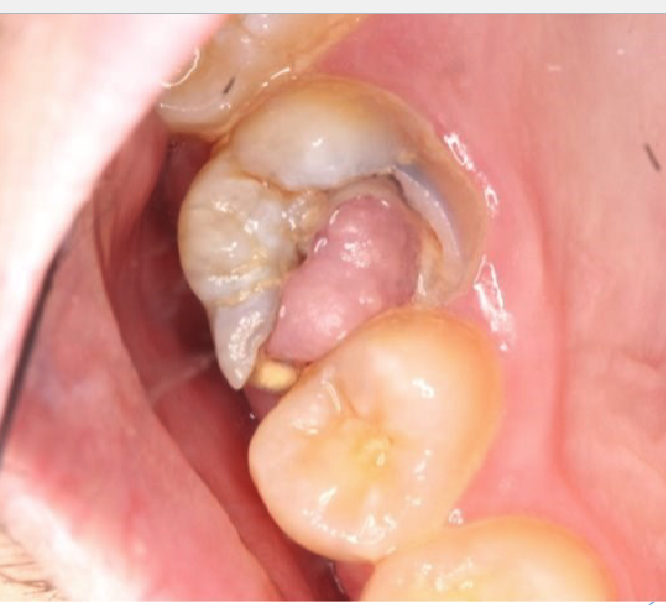

what is this

chronic hyperplastic pulpitis: hyperplastic granulation tissue extrudes from pulp chamber

chronic hyperplastic pulpitis usually happens in which age

children + young adults w/ large pulp exposures

2 tx options for chronic hyperplastic pulpitis

endo

ext